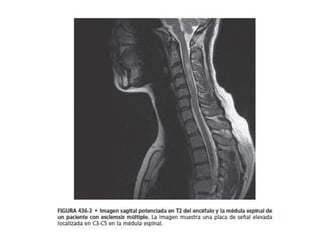

 La imagen por resonancia magnética (RM) encefálica resulta

extremadamente útil y debería realizarse en todos los pacientes en

los que la EM sea una consideración diagnostica.

 Mas del 95% de pacientes con EM clínicamente definida presenta

una RM encefálica anormal y la presencia de lesiones brillantes

hiperintensas es tan característica de la EM que una resonancia

cerebral normal debería sugerir un diagnostico alternativo.